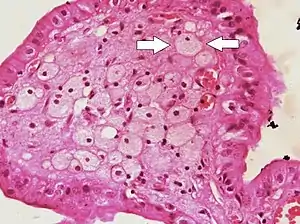

| Micrograph of cholesterolosis of the gallbladder, with an annotated foam cell. H&E stain. | |

The name strawberry gallbladder comes from the typically stippled appearance of the mucosal surface on gross examination, which resembles a strawberry. Cholesterolosis results from abnormal deposits of cholesterol esters in macrophages within the lamina propria (foam cells) and in mucosal epithelium. The gallbladder may be affected in a patchy localized form or in a diffuse form. The diffuse form macroscopically appears as a bright red mucosa with yellow mottling (due to lipid), hence the term strawberry gallbladder. It is not tied to cholelithiasis (gallstones) or cholecystitis (inflammation of the gallbladder).[2]